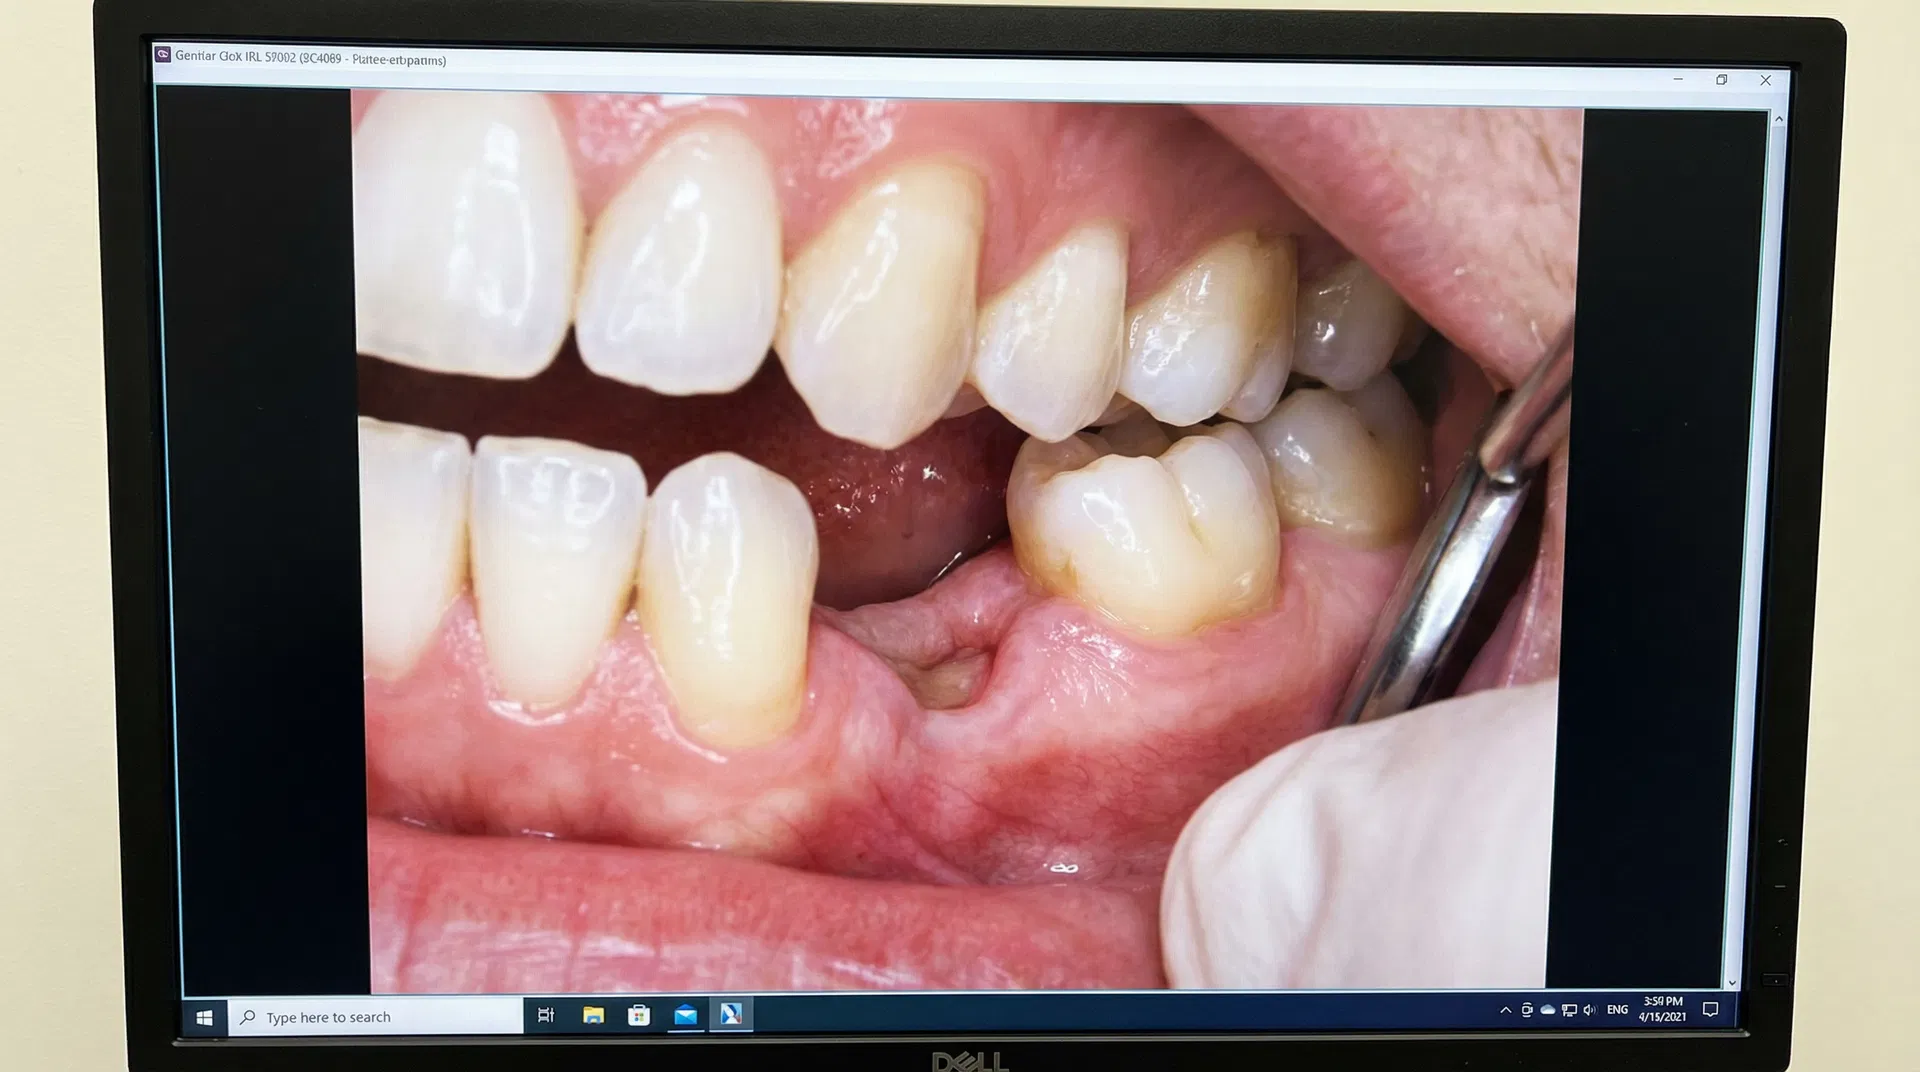

Before & After Transformations

See the life-changing results achieved by Dr. Nurein. Drag the slider to compare before and after treatment photos.

Note: Cases 2, 3, and 4 feature real patient results. Other cases are illustrative. Actual results may vary. Consult Dr. Nurein for a personalized assessment.

Comprehensive Dental Care

From routine check-ups to complex implant surgery — all your dental needs under one roof, delivered by a qualified specialist.

Periodontics

Expert treatment for gum disease, including scaling, root planing, and advanced periodontal therapy.